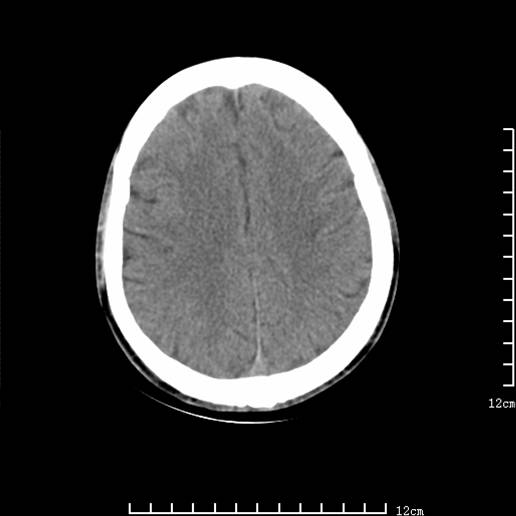

以下图像分别是3月25日凌晨及下午图像、3月27日、4月16日的ct图像。

3月27日

1)左侧额颞顶叶、岛叶及基底节区(相当于左侧大脑中动脉供血区)大面积脑梗塞。2)右侧基底节区腔隙性脑梗塞。

大脑中动脉供血区大面积脑梗塞没有问题。

资料齐全,符合脑梗塞溶栓治疗后,血管再通而致的出血性脑梗塞。

支持出血性脑梗塞,可能因血管再通后,再灌注损伤所致。